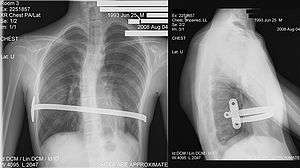

Through two small incisions in the side of the chest, an introducer is pushed along posterior to the sternum and ribs, and anterior to the heart and lungs. Then a concave stainless steel bar is slipped under the sternum, through the incisions in the side of the chest. A third, smaller incision is made to insert a thoracoscope (small camera) used to help guide the bar. Taller patients, older patients, or patients requiring extensive correction may receive two or more bars. All bars may be placed through two incisions or additional incisions may be made. The bar is then flipped, and the sternum pops out. To support the bar and keep it in place, a metal plate called a stabilizer may be inserted with the bar on one side of the torso. PDS sutures may also be used in addition to the stabilizer. The stabilizer fits around the bar and into the ribcage. The bar and stabilizer are secured with sutures that dissolve in about six months.

Some surgeons have achieved excellent results using only pericostal sutures, without the use of stabilizers.[2] For older children who have more ossified bones, an additional option the surgeon has is to make an incision across the sternum so the bar is attached with a wire to the sternum to avoid bar displacement. Older children's bones do not conform as easily to the bar, thus increasing the risk of bar displacement, so the wire attaching the bar directly to the sternum may help avoid a second surgery to correct bar displacement.

Eventually, the bar is secured with muscle tissue that regrows during the recovery time. Although initially recommended only for younger patients, the Nuss procedure is now commonly used on patients in their thirties and forties with excellent results.[3]:342–3

After a period of two to four years,[3]:343 the surgical stainless steel bar is removed from the patient's chest. This procedure lasts approximately ninety minutes. The length of time that the patient stays at the hospital following the bar removal procedure varies, depending on the amount of new bone growth surrounding the bar. Accordingly, the length of time may range from a few hours to several days, or up to one week.